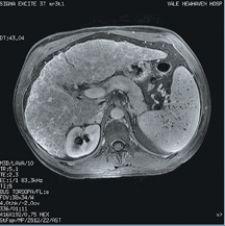

The next phase of MRI lays in identifying metastasis in the abdomen. The greatest challenge for abdominal MR exams is that one in 10 are rendered inconclusive due to motion artifacts or inadequate resolution. To remedy this problem, GE Healthcare has integrated its MR systems Signa HD 1.5T and Signa HD 3.0T with a new MRI software called LAVA (liver acquisition with volume acceleration). LAVA combines contrast-enhanced, multiphasic imaging with fat suppression for MR liver imaging. The MR system can scan the entire liver of a large patient in a single breath-hold, which is particularly helpful with patients who have difficulty holding their breath, and LAVA reportedly achieves 25 percent more resolution with 25 percent more coverage compared to other standard MR devices.